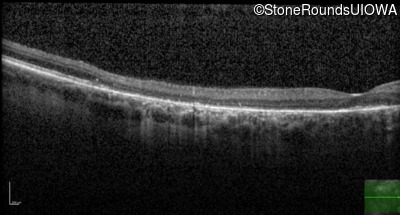

Optical Coherence Tomography - Right - 20/20 sc

Exemplar / OCT Stack